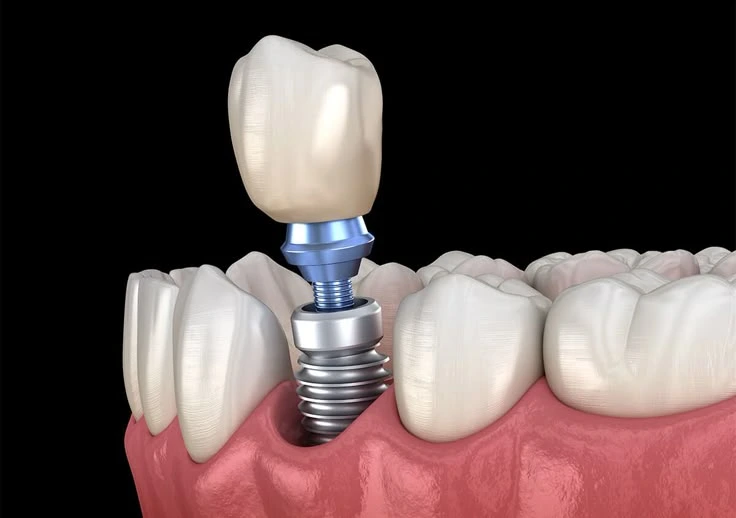

A dental implant is a titanium screw we place surgically into your jawbone where a tooth root used to be. Over the next 3-6 months, something remarkable happens. The implant fuses with your bone through a process called osseointegration. It literally becomes part of your jaw.

Once that’s happened, we attach a connector piece (called an abutment) to the implant, then crown it with porcelain matched perfectly to your natural teeth. The result is a replacement tooth that looks, feels, and functions exactly like the real thing.

Under local anaesthetic (you’re awake but completely numb), we make a small incision in your gum, create precise space in the bone, and place the titanium implant exactly where your tooth root was. We stitch the gum closed over or around the implant, depending on the technique. A temporary tooth (usually a removable partial denture or temporary bridge) fills the gap cosmetically whilst healing happens.

Appointment 1 (30-45 minutes): We expose the implant through a tiny incision (or it’s already exposed, depending on technique), attach an abutment (the connector post), and take impressions for your custom crown. Gums heal around the abutment for 1-2 weeks.

Appointment 2 (30-45 minutes): Your custom porcelain crown arrives from the laboratory. We attach it permanently to the abutment, check your bite carefully, and you’re done. You leave with your completed tooth.